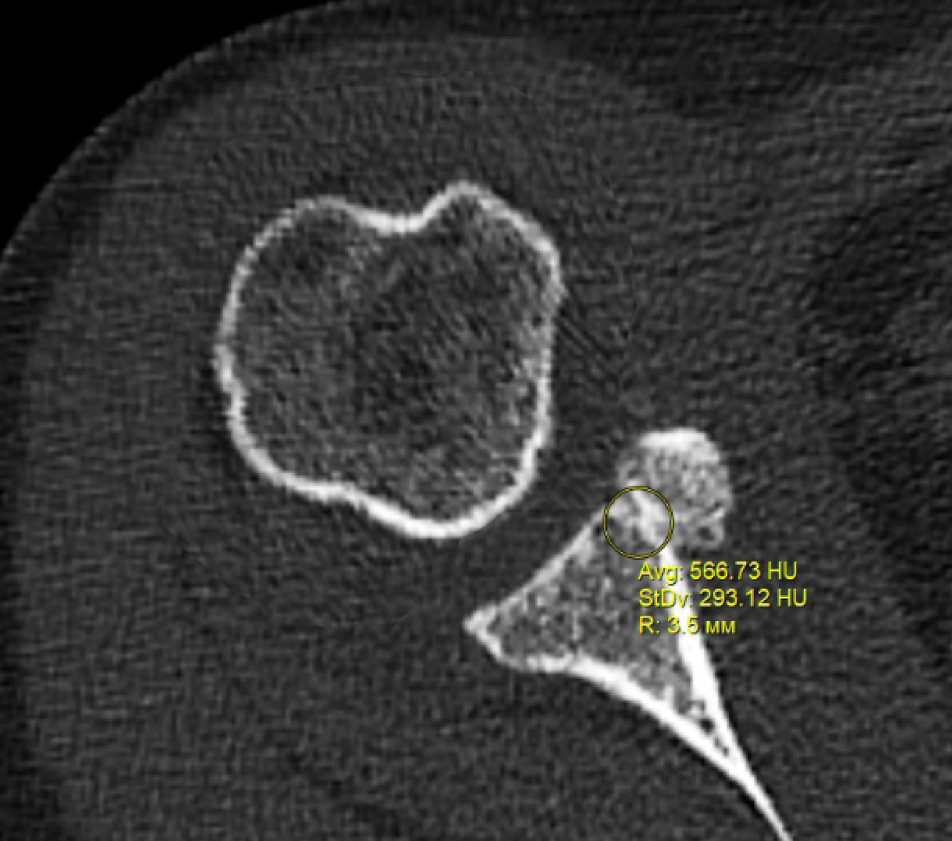

В программном обеспечении, на аксиальных КТ срезах оперированного плечевого сустава, выбирали инструмент «круг», который позволял посчитать среднюю плотность тканей внутри круга в единицах Хаунсфильда. Шкала единиц Хаунс-филда (HU) – шкалалинейного ослабления излучения по отношению к дистиллированной воде, рентгеновская плотность которой была принята за 0 HU (при стандартных давлении и температуре). Круг устанавливали таким образом, чтобы одна его половина была заполнена тканью гленоида, вторая половина тканью трансплантата (рис. 1–3). Оценивали плотность тканей над проксимальным винтом, между винтами, под дистальным винтом. Полученные данные анализировали с помощью пакета Microsoft Excel.

Рис. 2. Оценка плотности ткани между винтами

Через 3 месяца после оперативного лечения по данным анализа КТ срезов были получены следующие результаты: плотность ткани над проксимальным винтом составили (424 ± 24,3) HU, между винтами (460 ± 23,4) HU, под дистальным винтом (587 ± 49,1) HU. Спустя 6 месяцев после операции плотность ткани над проксимальным винтом составили (320 ± 28,7) HU, между винтами (424 ± 36,2) HU, под дистальным винтом (623 ± 33,4) HU. Через 12 месяцев после операции показатели были следующие над проксимальным винтом (276 ± 22,1) HU, между винтами (387 ± 31,1) HU, под дистальным винтом (662 ± 43,2) HU (таблица).